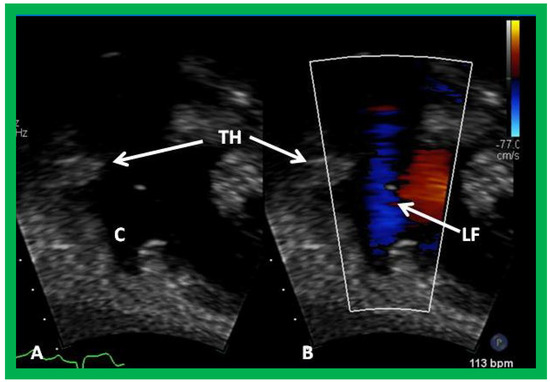

Figure 19. Selected video frames from suprasternal notch view demonstrating proximal shunt (PS) by color flow imaging (A). In a slightly different view, (B), the flow from the distal shunt (DS) into right (RPA) and left (LPA) pulmonary arteries is shown.

In patients who had an aorto–pulmonary shunt (most commonly modified Blalock–Taussig), the shunt may be visualized by color flow imaging (Figure 19), although it is difficult to image it only by 2D. High Doppler flow velocities across the shunt are normally recorded (Figure 20), and they reflect the systolic pressure difference between the aorta and PAs. Low Doppler flow velocities across the shunt, however, may indicate high PA pressures. The flow into branch PAs can easily be demonstrated by color flow Doppler imaging (Figure 19B). Flow acceleration in the branch PAs is usually seen (Figure 21) and is of no concern. However, high flow velocities may indicate branch PA stenosis.